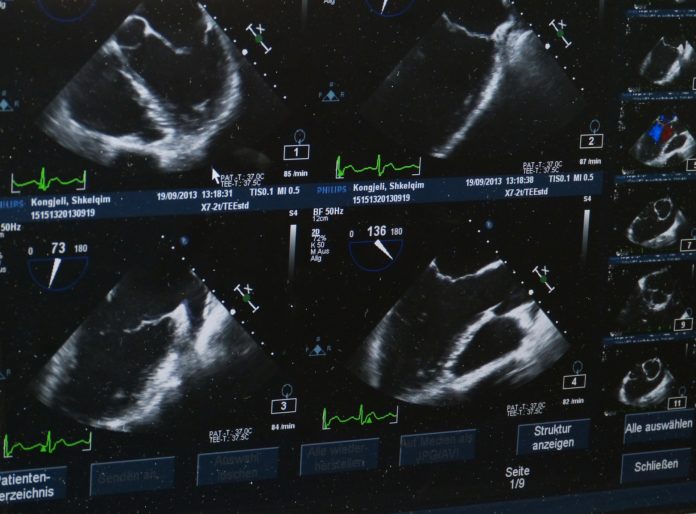

Bečko zdravstveno osiguranje omogućava ženama u glavnom gradu da ubuduće besplatno idu na ultrazvučni pregled. Doskoro su žene za godišnji pregled ultrazvukom morale da plate kod ginekologa od 35 do 40 evra.

Izmenom zakona omogućeno je da žene dobiju besplatan pregled ultrazvukom, što je, inače, bilo odranije besplatno za muškarce.

Mnoge žene zbog potrebe plaćanja ultrazvuka nisu odlazile redovno kod ginekologa.

Očekuje se da će do kraja godine besplatni pregled iskoristiti najmanje 150.000 žena.